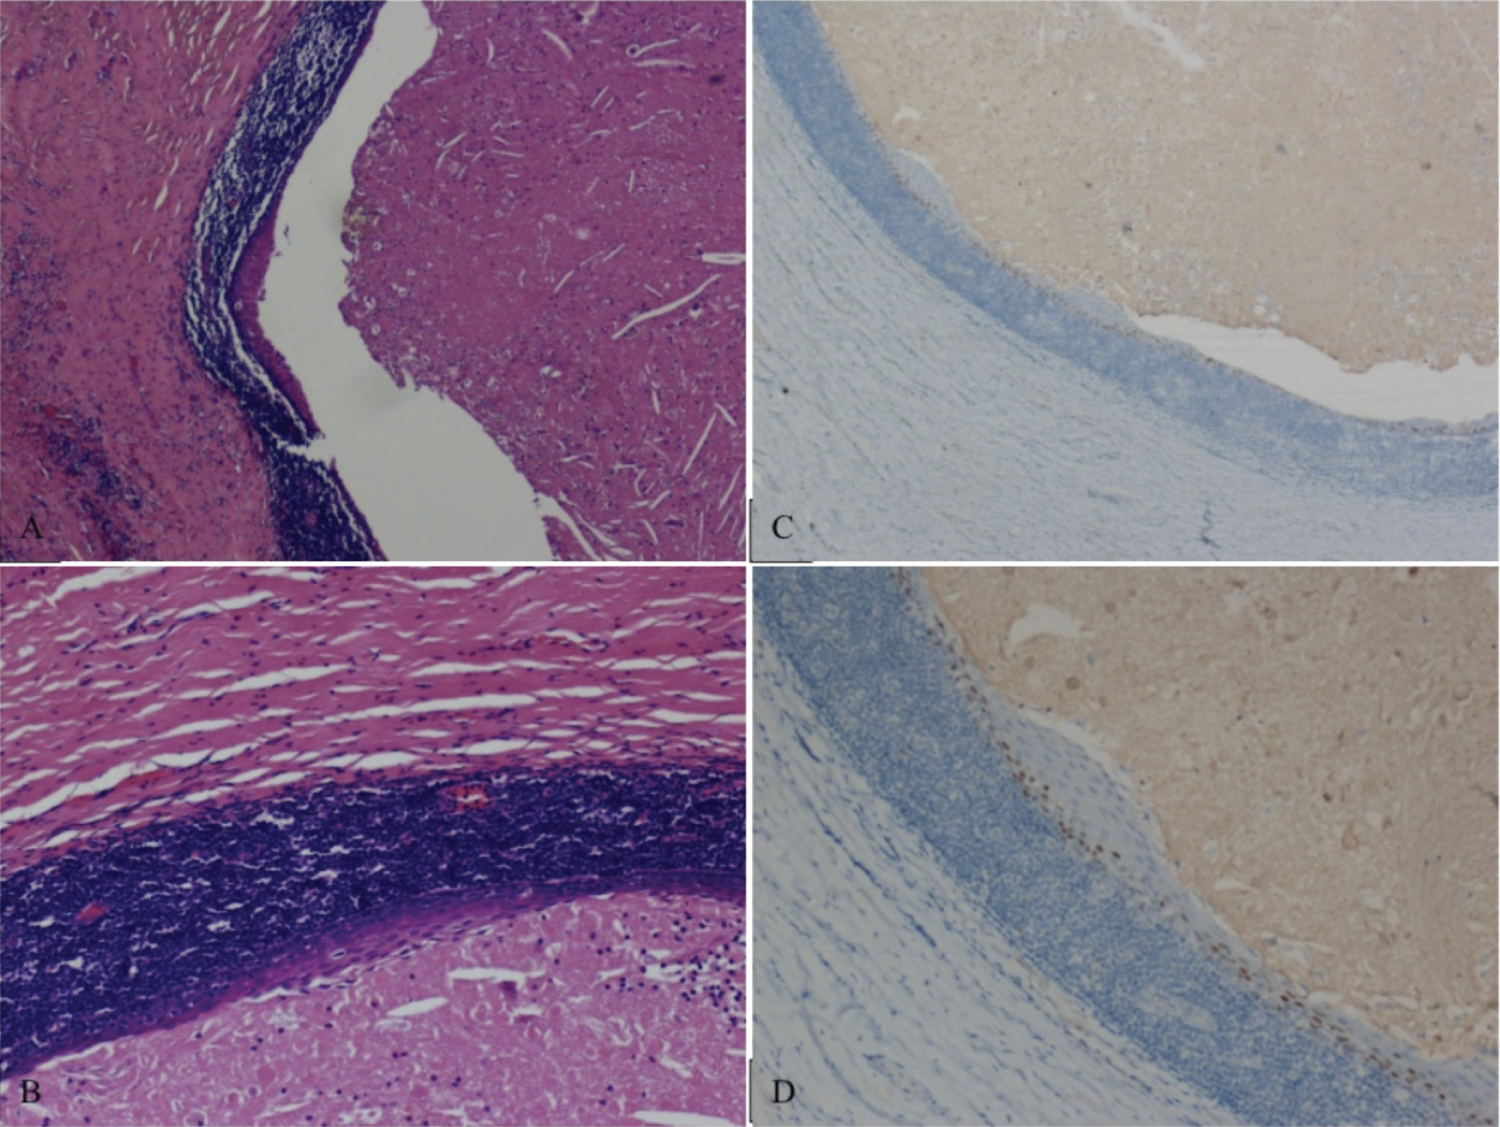

We report on a healthy 30-year-old pregnant woman who presented a right sided tense-elastic neck swelling, starting from the seventh month of pregnancy (Figure 1). The ultrasound examination demonstrated a 41 × 20 mm oval cystic formation characterized by corpuscular content, localized at right mandibular angle in a space between the submandibular and parotid gland. The formation shows no vascular enhancement at Doppler sampling, being compatible with a branchial cleft cyst arisen from the second cleft. Nearby structures were deemed normal, no lymphadenopathy was detected (Figure 2). An iterative clinical and ultrasound check demonstrated its progressive growth, reaching maximum expansion at delivery. The cyst did not cause any pain or functional impairment. MRI examination of the neck, conducted after delivery, confirmed the known cyst, 38 × 40 × 48 mm in size with an oval morphology and clear limits, without infiltrating characteristics, with a finely structured proteinaceous sedimentation, located at right lateral neck compartment, antero-medial to the sternocleidomastoid muscle. No significant loco-regional adenopathies were documented, the adipose layers were preserved, and the parotid and submandibular glands were free from focal alterations. These findings were compatible with Bailey type II second branchial cleft cysts [4,5,9,10] (Figure 3). After delivery, the cyst remained stable for about four months and then gradually shrunk within a month. Subsequently surgical excision was performed. The surgical material was sent for histological examination, which confirmed the diagnosis of second branchial cleft cyst and detected the positivity at immunohistochemistry for ER on the lining epithelium using anti-ERα (SP1) antibodies (Figure 4).

Figure 4: (A,B) Branchial cyst lined by keratinized stratified squamous epithelium with no evidence of adnexal structures (Magnifications A 4X, B 10X), H&E; C,D) Focal based expression of anti-Estrogen Receptors antibody (CONFIRM ER (SP1) Rabbit Monoclonal Primary Antibody) (Magnifications C 4X, D 10X), immunohistochemistry. View Figure 4